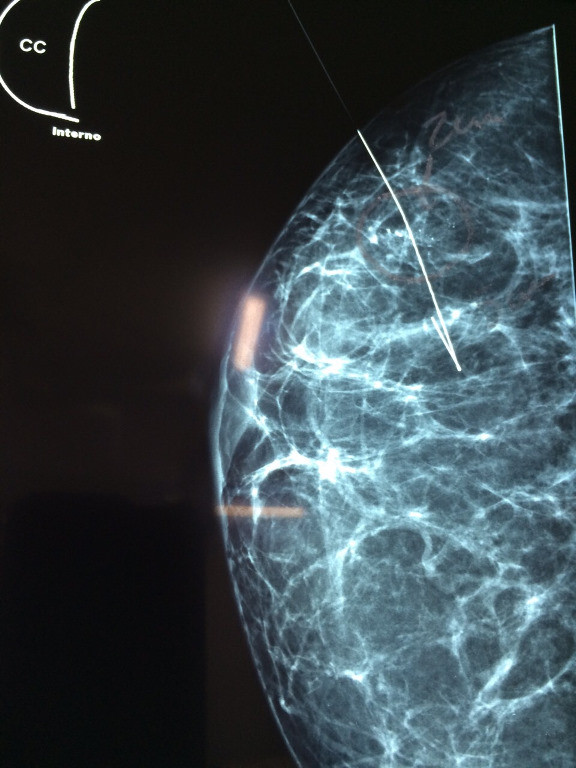

Mamografía de rutina con calcificaciones sospechosas.